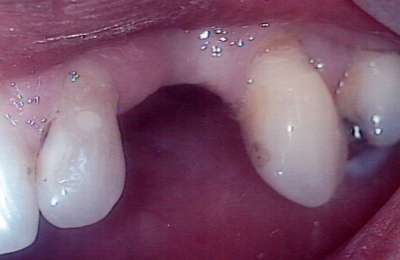

See the results

Drag the sliders below to see some of the amazing results achieved by other Lumino patients and our experienced team of dentists.

Bridge 1 Before Bridge 1 After

Bridge 2 Before Bridge 2 After

Bridge 3 Before Bridge 3 After